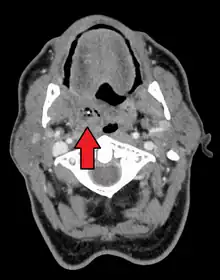

Absceso periamigdalino

El absceso periamigdalino es una acumulación de material infectado alrededor de las amígdalas palatinas.[2][1] El absceso periamigdalino generalmente se debe a una infección por varios tipos de bacterias. A menudo sigue a una faringitis estreptocócica. Por lo general, no ocurren en personas que se han sometido a una amigdalectomía. El diagnóstico generalmente se basa en los síntomas. Se pueden realizar imágenes médicas para descartar complicaciones.

Absceso periamigdalar del lado derecho | ||

Se suele descubrir al inspeccionar la orofaringe (garganta) presentando hinchazón en un lado y en el paladar. La úvula puede estar desplazada.[8]

- Tomografía computarizada